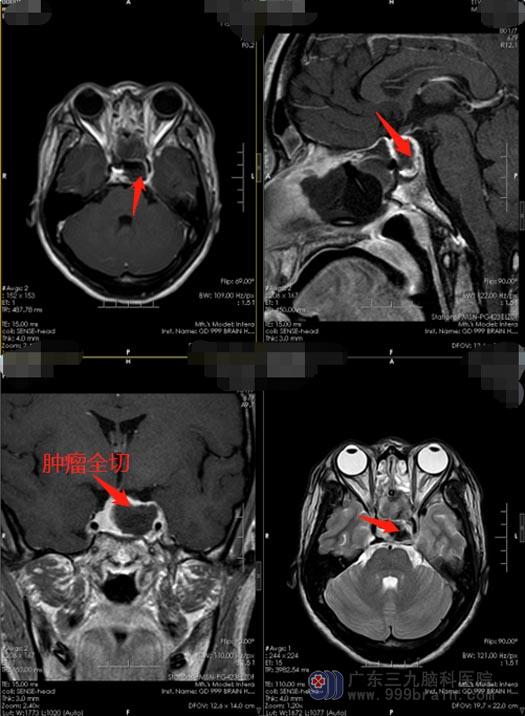

▲术后